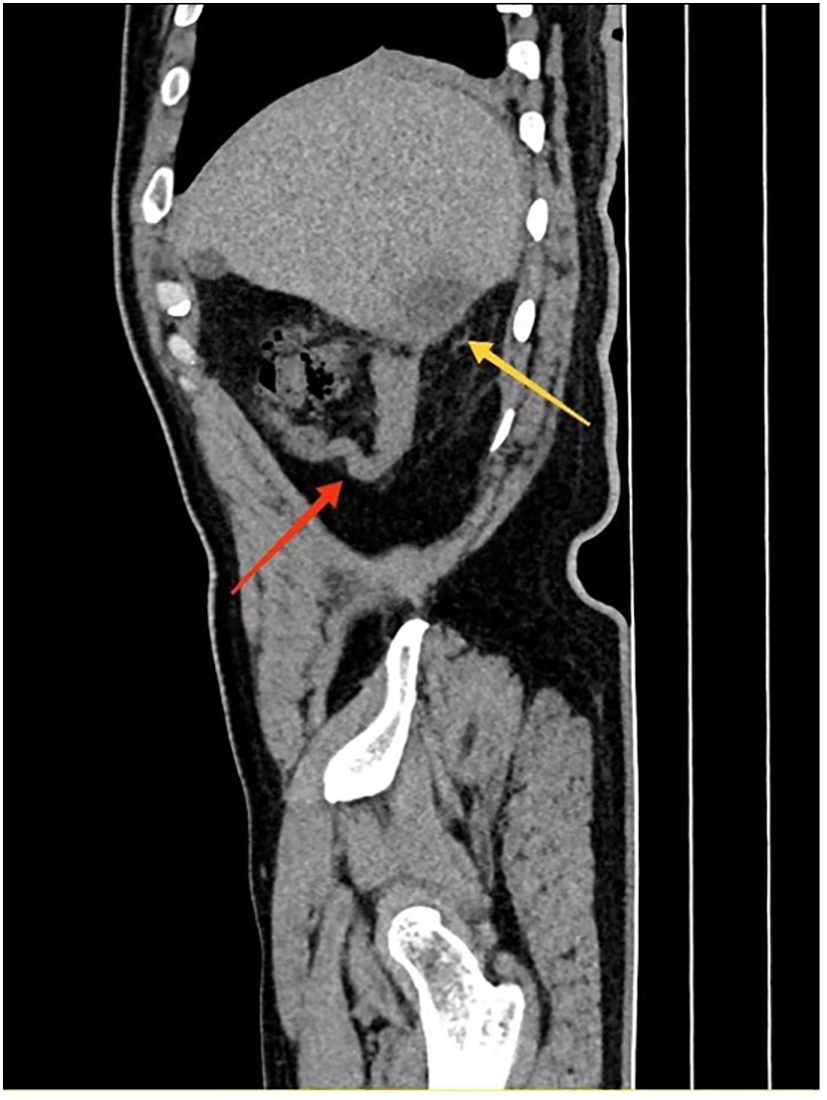

A 56-year-old male patient was admitted to the hospital on February 28, 2025, with the chief complaint of “right abdominal pain accompanied by fever for 2 weeks.” Two weeks prior, the patient developed right abdominal pain without any obvious trigger, which persisted and was unrelieved, accompanied by fever, with a maximum temperature of 39°C. He did not experience chills, had cloudy urine, but did not report urinary frequency, urgency, dysuria, nausea, vomiting, or diarrhea. The patient has no history of night sweats, no recent weight loss, and no previous symptoms of chronic abdominal pain. The patient had a body mass index (BMI) of 29.4, with no history of smoking or alcohol consumption. He had no significant past medical history and reported no known familial or hereditary disorders. The patient sought medical attention at a local hospital, where a urinary system CT(Computed Tomography) scan revealed bilateral kidney stones. He was diagnosed with “bilateral kidney stones complicated by urinary tract infection” and was treated with cefotaxime for 10 days, but his pain did not show significant improvement. He later presented to our emergency department, where a non-contrast abdominal and pelvic CT scan (Figures 1, 2) revealed acute appendicitis (subhepatic appendix) and a hepatic abscess in segment VI measuring approximately 22 mm × 29 mm. He was admitted to our department for further diagnosis and treatment.

Figure 2

Sagittal CT showing subhepatic appendicitis (red arrow) with associated hepatic abscess in segment VI (yellow arrow).